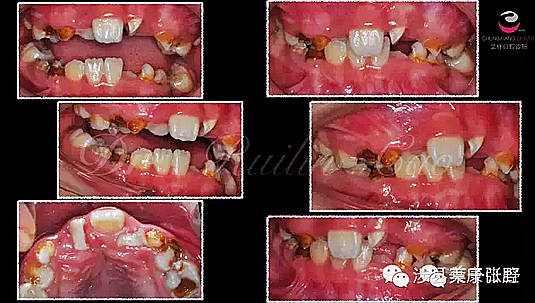

網(wǎng)友又不明白了,什么叫吸收消失?看x片看不懂哎......

黑色部分表示那里的骨頭感染已經(jīng)爛沒(méi)有了,消失了,牙胚應(yīng)該在健康頜骨里孕育生長(zhǎng)發(fā)育,現(xiàn)在在感染的病灶里生長(zhǎng),在膿水里侵泡。

又有好奇網(wǎng)友問(wèn)他怎么有那么多牙?

乳牙下面有恒牙孕育著。